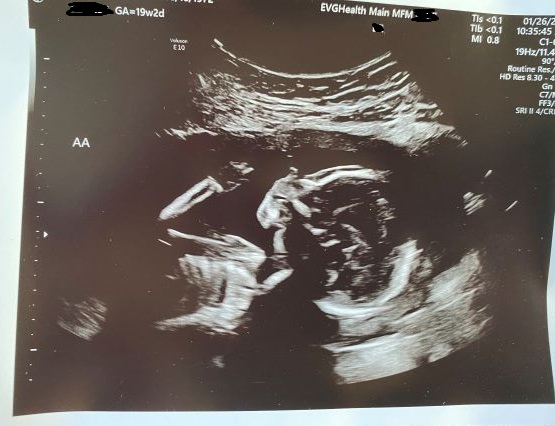

01/26/2021: 19w2d Dopplers return to normal but sIUGR diagnosis confirmed

With normalized Dopplers, this week the TAPS diagnosis is put on the back burner along with TTTS. However, sIUGR is confirmed because Baby A’s growth falls below the 10th percentile, the diagnosis of Selective Intrauterine Growth Restriction (sIUGR) is confirmed. While sIUGR and our babies have Type 3.

Our treatment path is currently Expectant Management. As we do weekly or more frequent monitoring, conditions may change. Because the artery to artery flows between the babies are likely keeping Baby A alive, we will not consider surgery, because it is aimed at preserving Baby B because Baby A isn’t likely to survive. Only if it appears that Baby A will not survive would we consider surgical options of FLP or Cord Occlusion. FLP is still a choice until the vessels become too large or if my placenta is too complicated to allow FLP. Which would leave us with cord Cord Occlusion: to be clear this laser sealing of Joshua’s umbilical cord along with lethal injection – it’s choosing to humanely end our baby’s life in the hope we can save Daniel.

These words below are so sterile and clinical but they mean choosing a car seat and a casket, or two caskets. In real life, these words are heart rending to the woman carrying these babies, seeing them on ultrasound with all of their fingers and toes, ears and lips, fully formed, approx. 10 inches long, occasionally sucking their thumbs or touching each other. They are my babies and I want to hold them, see them grow, hear them giggle, kiss their owies and hear them say “all better.” As a mom, I must hold the reality of losing them in one hand and the reality of their survival in the other every day and somehow remain sane in the duality.